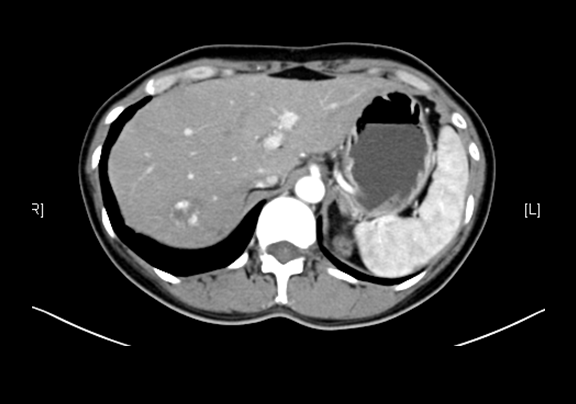

辅助检查:2015-12-07

上腹部增强CT示:肝右叶海绵状血管瘤可能性大;肝囊肿;左肾上极肿瘤可能性大;双肾多发囊肿。

术前CT检查:

动脉期